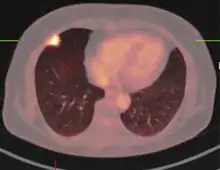

If there is an intermediate risk of malignancy, further imaging with positron emission tomography (PET scan) is appropriate (if available). It can be done simultaneously as a CT scan in the form of PET-CT. Around 95% of patients with a malignant nodule will have an abnormal PET scan, while around 78% of patients with a benign nodule will look normal on PET (this is the test sensitivity and specificity).[15] Thus, an abnormal PET scan will reliably pick up cancer, but several other types of nodules (inflammatory or infectious, for example) will also show up on a PET scan. If the nodule has a diameter of less than one centimeter, PET scans are often avoided because of an increased risk of falsely normal results.[15][16][17] Cancerous lesions usually have a high metabolism on PET, as demonstrated by their high uptake of FDG (a radioactive sugar).

- PET-CT of a tuberculoma.